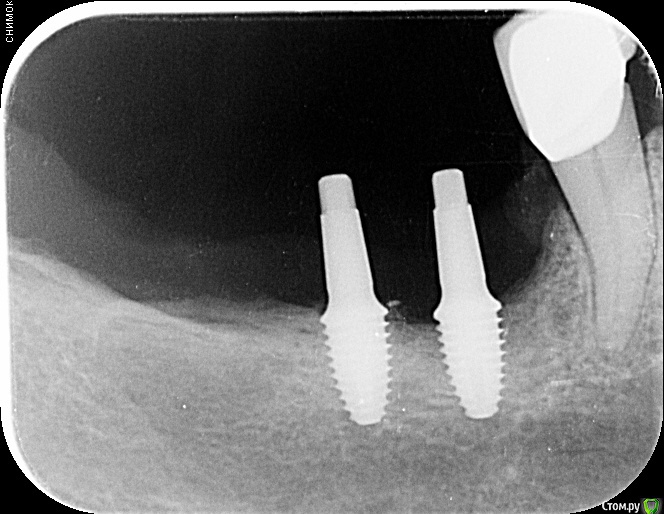

annda Опубликовано 1 августа, 2020 Поделиться Опубликовано 1 августа, 2020 (изменено) В подобной ситуации[ близко нерв, еще ближе , чем в теме,правда,не было 7ки)) поставила дентиумовский неразборный slim line,4х6. Запротезировала, как два премоляра. Прикольно получилось. Все на защелках,коронки истинные ВОРТ получились )Снимки попозже покажу,если нужно. Изменено 1 августа, 2020 пользователем annda 1 Ссылка на комментарий

Дмитрий М Опубликовано 2 августа, 2020 Поделиться Опубликовано 2 августа, 2020 В подобной ситуации[ близко нерв, еще ближе , чем в теме,правда,не было 7ки)) поставила дентиумовский неразборный slim line,4х6. Запротезировала, как два премоляра. Прикольно получилось. Все на защелках,коронки истинные ВОРТ получились )Снимки попозже покажу,если нужно. покажите снимки пожалуйста Ссылка на комментарий

Fin Опубликовано 2 августа, 2020 Автор Поделиться Опубликовано 2 августа, 2020 нет, берите зеленый. Standart Plus WN тело 4.8, шейка 6.5Большое спасибо за совет, понял Вас. Наверное наилучший вариант в данной ситуации. В подобной ситуации[ близко нерв, еще ближе , чем в теме,правда,не было 7ки)) поставила дентиумовский неразборный slim line,4х6. Запротезировала, как два премоляра. Прикольно получилось. Все на защелках,коронки истинные ВОРТ получились )Снимки попозже покажу,если нужно. Интересно, покажите пожалуйста) Ссылка на комментарий

annda Опубликовано 3 августа, 2020 Поделиться Опубликовано 3 августа, 2020 (изменено) Стоял до этих имплантатов суперлайн коротыш 7мм,одиночка.Заколебались с раскруткой винта,ходила каждый месяц.Плюнула,решили выкрутить,переставить на эти.КТ после удаления. Изменено 3 августа, 2020 пользователем annda 1 Ссылка на комментарий

annda Опубликовано 4 августа, 2020 Поделиться Опубликовано 4 августа, 2020 Что-то с загрузкой пошло не так,извините.Контроль после постановки и контроль с абатментами(через 3 месяца) Ссылка на комментарий